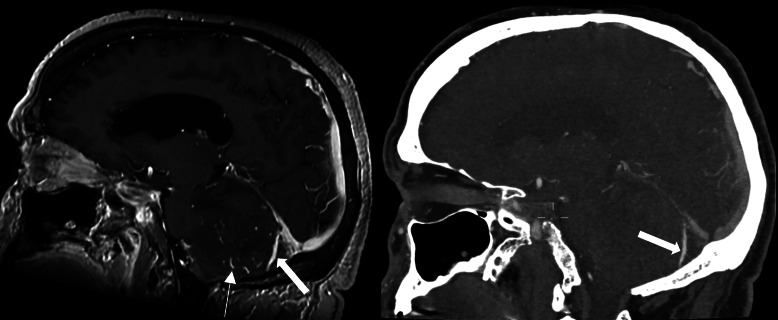

We report the case of a 45-year-old man with a rare cerebellar dural arteriovenous fistula (dAVF) presenting with dizziness and gait imbalance. MRI revealed a hemorrhagic lesion compressing the fourth ventricle. Digital subtraction angiography confirmed a Borden Type III dAVF, which was successfully treated by balloon-assisted embolization using PHIL 25%. This case draws attention to the importance of early diagnosis and intervention in posterior fossa dAVFs. Teaching point: Cerebellar dAVFs, though rare, harbor a high risk of hemorrhage and require prompt imaging and endovascular treatment.